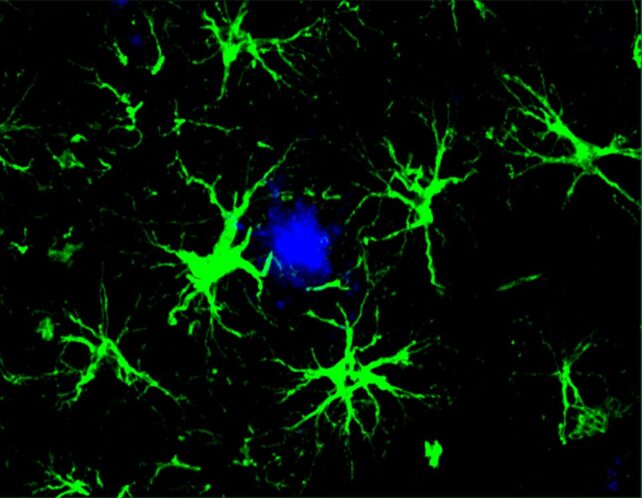

image of astrocytes targeting protein linked to Alzheimer's disease

The cellular immunotherapy turns astrocytes (green) into super cleaners that sweep away Alzheimer’s-related proteins. The cells successfully reduced the amount of harmful amyloid beta plaques (blue) in the brains of mice. (Yun Chen/Washington University)

Upon receiving this new assignment, astrocytes became singularly focused on clearing out amyloid beta plaques, a task at which they proved adept.